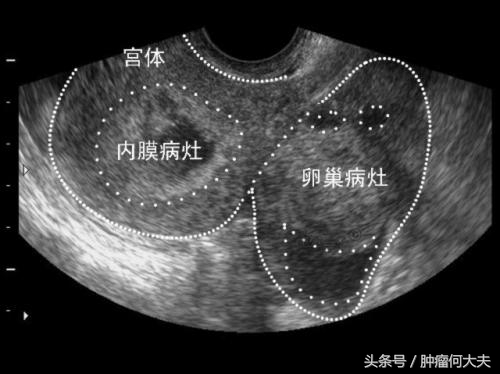

妇科B超检查

子宫内膜癌的病理学类型与转移扩散情况如何?子宫内膜癌组织学类型分为腺癌、腺棘癌、腺鳞状细胞癌、透明细胞癌、乳头状浆液腺癌、鳞状细胞癌、未分化癌。腺癌是子宫内膜癌常见的组织学类型,约占90%。子宫内膜鳞状细胞癌罕见,应与子宫颈鳞状细胞癌官腔内侵犯相鉴别。癌组织细胞分化程度分3级,G1:高度分化型癌;G::中度分化型癌;G3:未分化型癌。子宫内膜癌转移扩散途径有直接扩散:经子宫腔直接扩散到宫颈,或沿输卵管转移到卵巢及腹膜腔内。癌肿浸润子宫体肌层组织,可穿透子宫浆膜层扩散累及子宫旁组织;还有经淋巴道转移:经盆腔淋巴结扩散到腹主动脉旁淋巴结,或直接转移至腹主动脉旁淋巴结;血行转移不常见,血行转移的常见部位是肺、骨、肝、脑等器官。